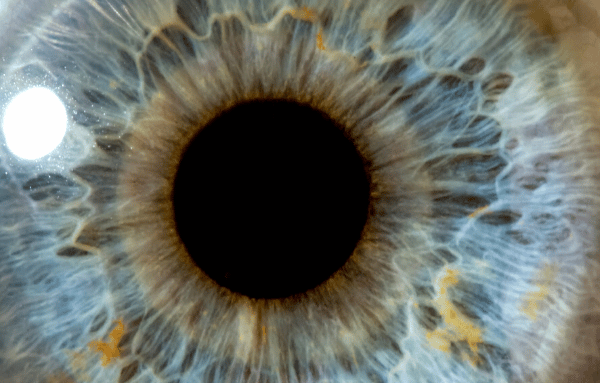

Au centre de l’œil, un gel transparent, le vitré, occupe près de 80 % du volume de l’organe. Ce gel, attaché à la rétine par des fibres microscopiques, assure la cohésion interne de l’œil. Un décollement postérieur du vitré, souvent abrégé en DVP, se définit par la séparation du vitré de la rétine, modifiant l’équilibre fragile de la structure oculaire.

Le vitré, à première vue anodin, est en réalité une matrice complexe : 99 % d’eau, 1 % d’acide hyaluronique et de collagène insoluble. S’y ajoutent glycoprotéines, protéines solubles et une population cellulaire nommée hyalocytes. Ce fragile équilibre assure au vitré sa transparence et sa consistance si particulière.

Bague de Weiss : lors de l’examen, le décollement complet du vitré au niveau du nerf optique donne naissance à une structure flottante bien visible : l’anneau de Weiss. Ce cercle translucide témoigne de la séparation, tandis que les zones d’adhérence résiduelles subissent des tractions, parfois à l’origine de complications.

Les corps flottants correspondent à des opacités du vitré qui projettent une ombre sur la rétine. Ils prennent la forme de taches, filaments ou structures évoquant une toile, surtout perceptibles sur fond clair. Ces opacités résultent de cellules résiduelles, de condensations de collagène ou parfois de l’anneau de Weiss.